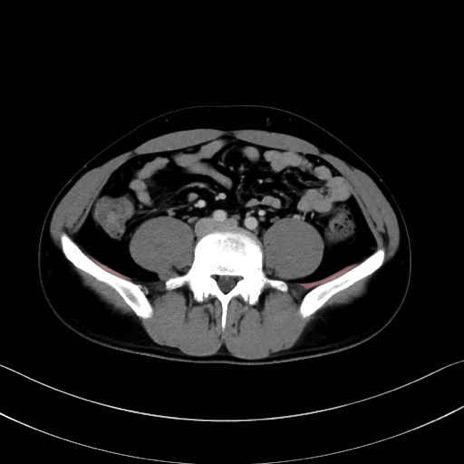

2. 腸腰筋群と骨盤底筋

大腰筋 (Psoas major)

腸骨筋 (Iliacus)